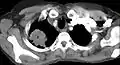

電腦斷層扫描显示一名47岁女性吸烟者患有潘科斯特肿瘤(标记P處:非小细胞肺癌,右肺)

電腦斷層扫描显示一名47岁女性吸烟者患有潘科斯特肿瘤(标记P處:非小细胞肺癌,右肺)